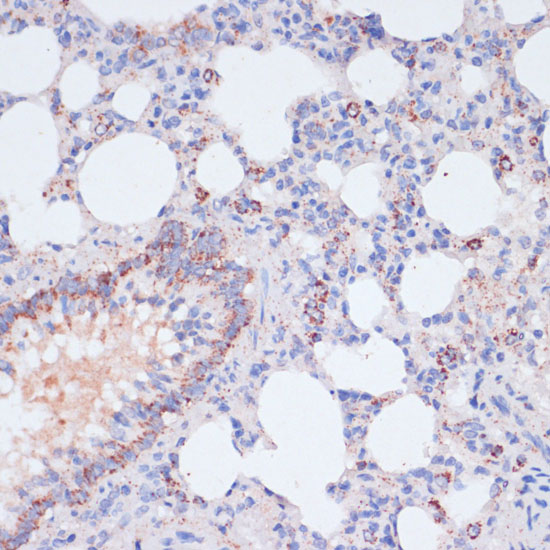

Immunohistochemistry of paraffin-embedded rat lung using VASP at dilution of 1:100 (40x lens).

Immunohistochemistry of paraffin-embedded rat kidney using VASP at dilution of 1:100 (40x lens).

Immunohistochemistry of paraffin-embedded human liver cancer using VASP at dilution of 1:100 (40x lens).

Immunohistochemistry of paraffin-embedded human colon carcinoma using VASP at dilution of 1:100 (40x lens).

Immunohistochemistry of paraffin-embedded mouse heart using VASP at dilution of 1:100 (40x lens).